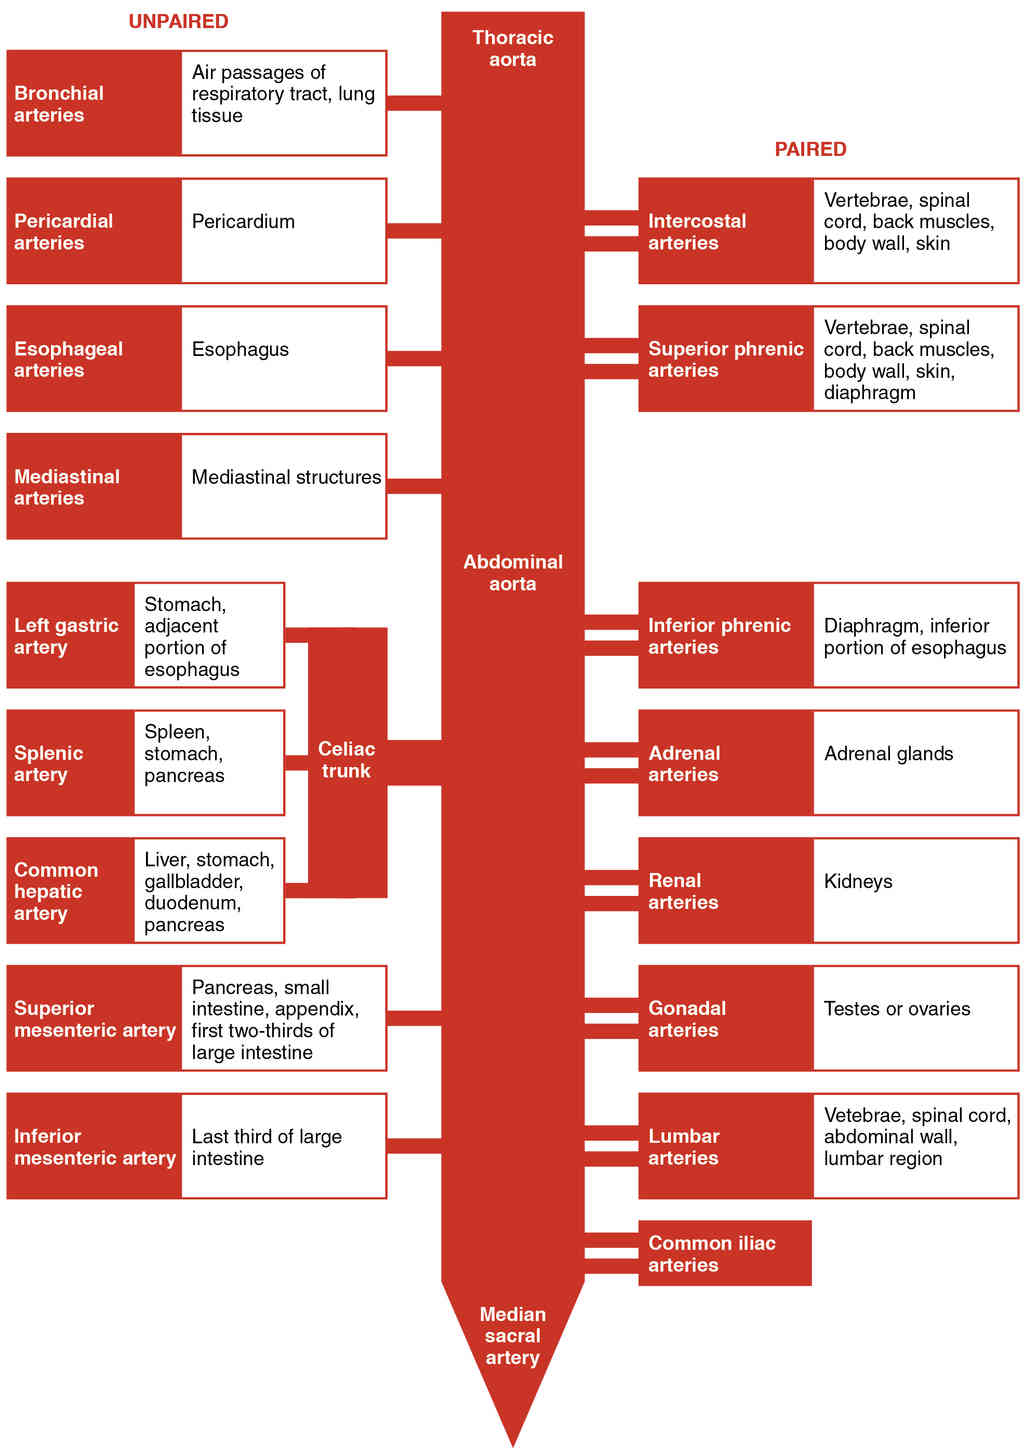

This page is under construction. For now, it is just a resource of the images found in the OpenStax Anatomy and Physiology Handbook. It wil slowly change into a revision tool. Each slide has a number. Use this to refer to the slide. When completed, it will have an unlabelled section, with labelled slides in parallel. On the unlabelled slides, write your answer and use the labelled slide to assess yourself. Keep track by also noting the number on each slide. Improvement at each attempt is important, more so than full marks on a first attempt.